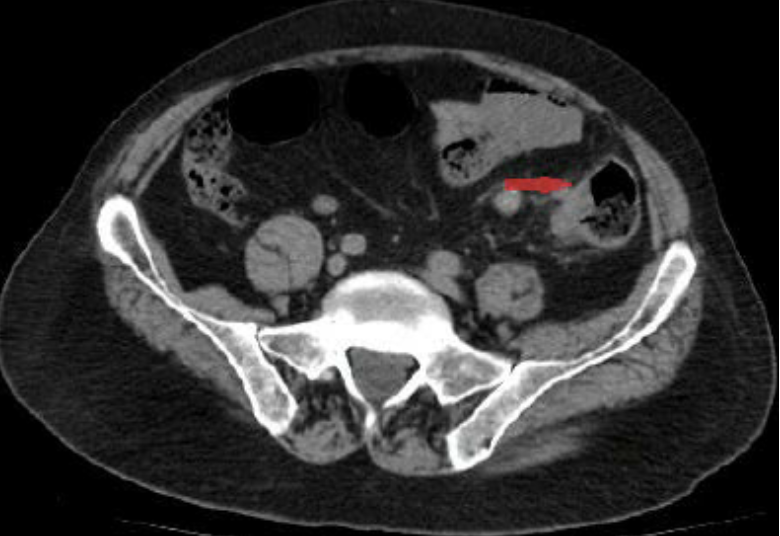

Acute appendicitis

CT Abdomen/Pelvis IV contrast

Diverticulitis

CT Abdomen/Pelvis IV contrast